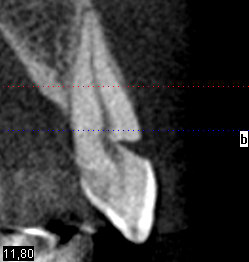

en visualisant un cone beam, j'ai trouvé sympa cette image.

Non pas de symptômes, la pulpe nous montre ici qu'elle peut parfois prendre un certain recul :)

va falloir agir quand même.